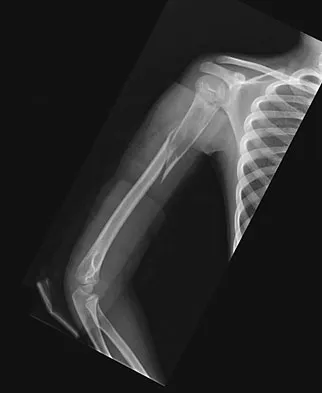

An 11-year-old boy has right shoulder pain and has been unwilling to use the arm after throwing a baseball in a Little League game 3 weeks ago. Examination reveals upper arm and shoulder tenderness with swelling. A radiograph and MRI scan are shown in Figures 27a and 27b. Management should consist of

The radiograph is consistent with a unicameral (simple) bone cyst. The MRI scan reveals that the cyst is juxtaposed to the physis and therefore can be classified as active (latent cysts are more than 1 cm away from the physis). Active cysts are treated with aspiration and steroid injection, although repeated injections may be necessary. Curettage and bone grafting results in more reliable healing but may lead to growth arrest in active cysts. Iannotti JP, Williams GR: Disorders of the Shoulder: Diagnosis and Management, ed 1. Philadelphia, PA, Lippincott Williams & Wilkins, 1999, pp 945-946.